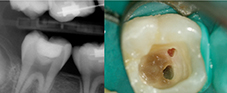

Photo 4 :Cas n° 2 : État initial.

Photo 5 : Cas n° 2 : Coiffage pulpaire.